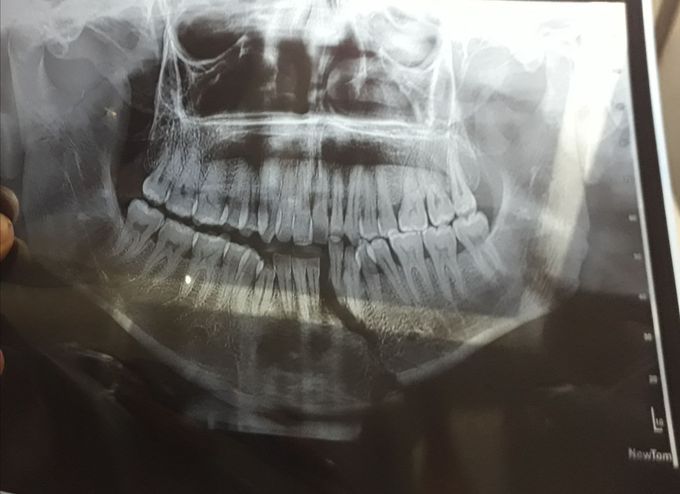

Mandible fracture

A case of RTA x ray shows mandible#

Fracture

In

Mandible